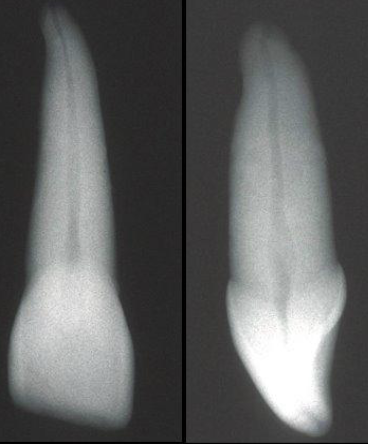

What is the root shape of canines?

Long root, usually apical curvature

Why might it be difficult to radiographically interpret canine apices?

Due to a small root tip